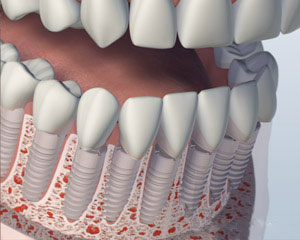

另一种选择涉及将四到六种植体, 这取决于你的下巴大小或形状, 进入你的下颚. 后完全愈合, 植入物与一个特制的支撑杆连接. 你的假牙将与附着到支撑条特殊的内部固定夹进行, 使假牙牢固卡入到位. 这就是所谓的 “覆盖义齿.” 这个方案的优点是,它更稳定比第一个选项,允许非常小的义齿运动. 你的义齿仍然是可拆卸,便于清洁和维护.

2. 植入放置

第三种选择包括将五个或更多的植入物在你的下巴和安装永久假牙. 假牙代替由它固定在支撑柱或棒螺钉或扣环举行. 它不接触牙龈组织, 它可以让你的假牙清洁下而不删除它. 这假牙将替换所有丢失的下齿,除了在维护访问将不会被删除. 虽然清洁假牙下,而不移除它耗费更多的时间和需要更多的灵活性, 谁想要一个永久性的义齿很多患者喜欢这个选项.

2. 植入放置

最后一个选项是让所有你的牙齿单独更换,使他们看起来是生长出来的牙龈组织,将最相似的天然牙的外观. 此选项通常需要八个或更多 植入物. 单独的基牙或这些植入物中的每一个支撑柱将被制成,每个缺齿冠将被放置. 牙齿往往是结合在一起的 窦嫁接 更换骨高度实力作支撑. 总体, 这是最昂贵的选择, 因为它需要最植入物和个体替代牙制作. 您所更换的选项也可以通过您的颌骨的电流大小和形状的限制.

2. 植入放置